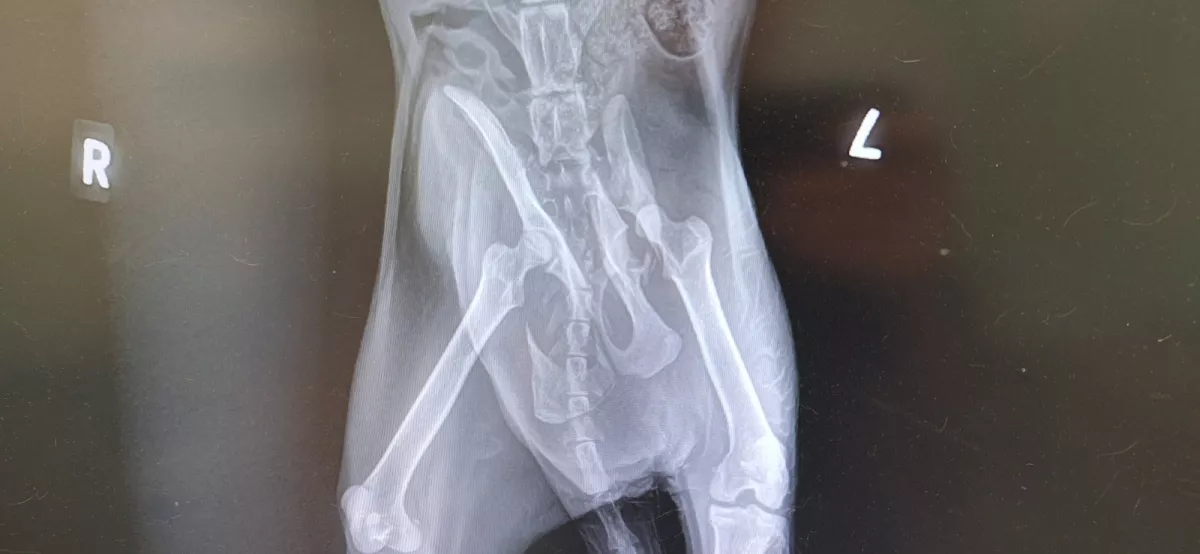

Доброволци, притекли се на помощ, са транспортирали животинчето до ветеринарна клиника, където рентгеновите фотоси демонстрират съществени увреждания – тежко строшаване на таза на няколко места. Единственият късмет за възобновяване е комплицирана интервенция, която би трябвало да се извърши на два стадия.